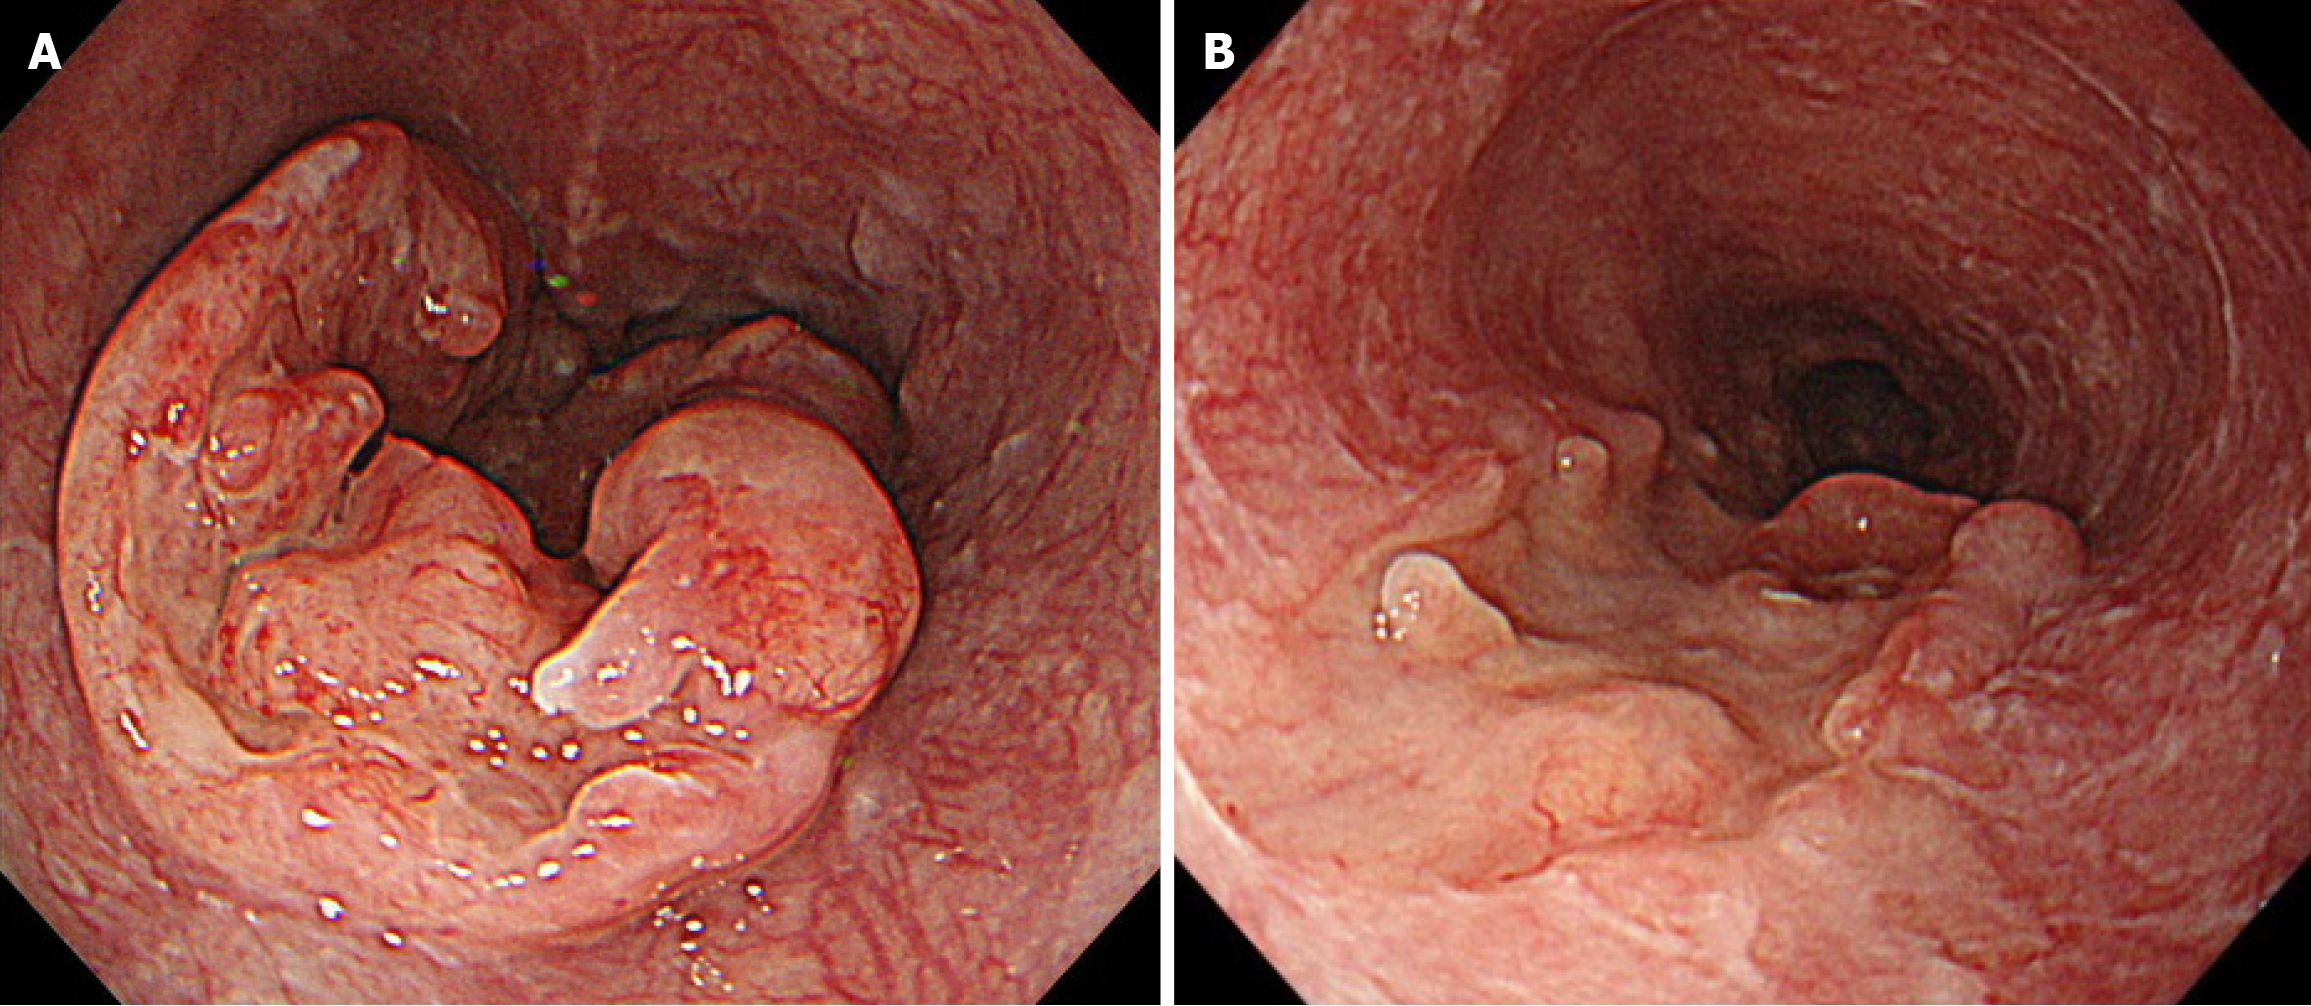

EGD revealed a semicircular, type 3 tumor in the middle thoracic esophagus, located 29-36 cm from the incisors (Figure 1A). Histopathological analysis of the biopsy specimen confirmed SCC. Computed tomography (CT) revealed irregular wall thickening from the middle to the lower thoracic esophagus, corresponding to the primary lesion (Figure 2A). In addition, an enlarged No. 101L lymph node measuring 15 mm was observed (Figure 2B), along with bulky suprapancreatic lymph node metastasis involving No. 8 and No. 9, forming a mass; furthermore, No. 11p was enlarged to 35 mm and showed direct invasion into the pancreatic body (Figure 2C-F). No other distant metastases were observed. On the basis of these results, the patient was diagnosed with locally advanced unresectable esophageal cancer of the middle thoracic esophagus [cT4a (No. 11p-pancreas) N4M0 cStage Iva][10,11].

Initially, we planned to administer chemotherapy, and conversion surgery would be considered if the tumor became resectable following the chemotherapy. The induction chemotherapy involved docetaxel + cisplatin + 5-fluorouracil (DCF) (docetaxel 70 mg/m2/day on day 1, cisplatin 70 mg/m2/day on day 1, and 5-fluorouracil 750 mg/m2/day on days 1-5). After three courses of DCF chemotherapy, EGD and CT revealed shrinkage of the primary lesion (Figures 1B and 3A). Additionally, CT demonstrated a remarkable reduction in the size of the metastases involving No. 101L, No. 8, and No. 9. In contrast, the No. 11p lymph node showed only slight shrinkage (Figure 3B and C). Positron emission tomo